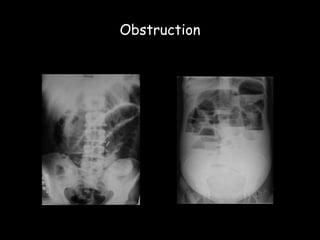

Imaging in Small Bowel Obstruction

 20% of patients presenting with acute

abdomen

 1st investigation- plain radiographs

Obstruction

Adhesions

Hernias